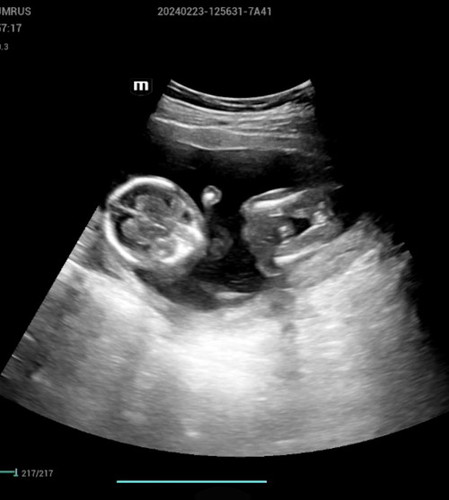

16 สัปดาห์รู้เพศได้กี่เปอเซนคะ

บ้านนี้รู้ตอน 12 สัปดาห์ค่ะ 96%